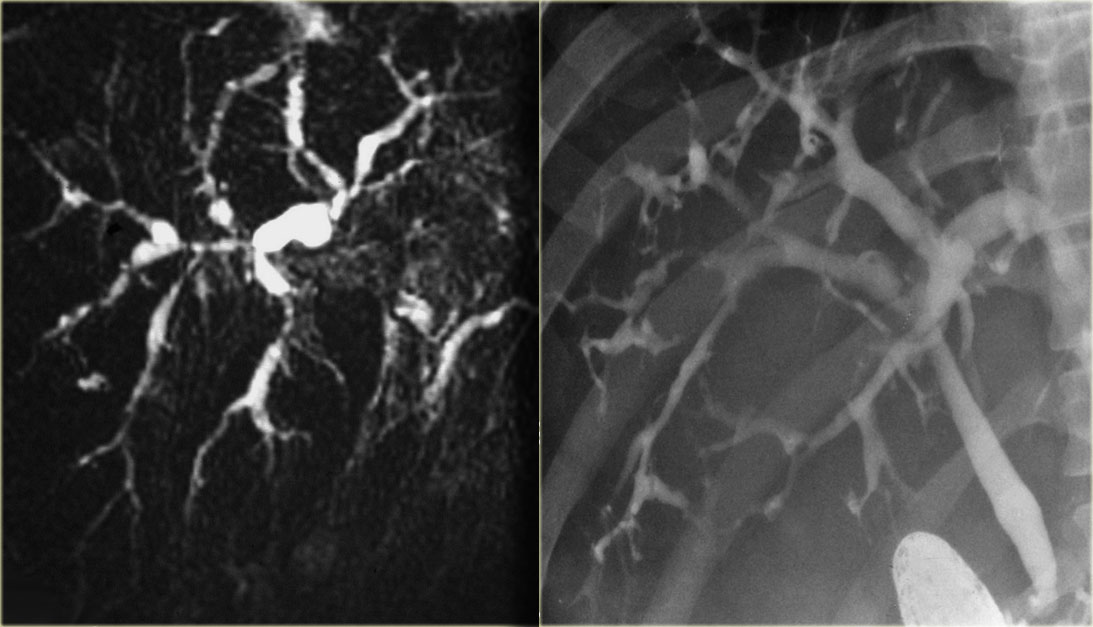

पीएससी का निदान कोलेजनोग्राफी के माध्यम से किया जाता है, जिसमें पित्त नलिकाओं में डाई इंजेक्ट करना और एक्स रे लेना शामिल होता है। कोलेजनोग्राफी को एक एंडोस्कोपिक प्रक्रिया (एंडोस्कोपिक रेट्रोग्रेड कोलेजनोपैंक्रेटोग्राफी, ईआरसीपी) के रूप में, रेडियोलॉजी या सर्जरी के माध्यम से, या चुंबकीय अनुनाद इमेजिंग (एमआरआई) के साथ किया जा सकता है। ) स्कैन उपचार में खुजली से राहत देने के लिए दवा, संक्रमण का इलाज करने के लिए एंटीबायोटिक्स और विटामिन की खुराक शामिल है, क्योंकि पीएससी वाले लोगों में अक्सर विटामिन ए, डी और के की कमी होती है। कुछ मामलों में, सामान्य पित्त नली में प्रमुख रुकावटों को खोलने के लिए सर्जरी भी की जाती है। यदि लिवर ख़राब होने लगे तो लिवर प्रत्यारोपण एक विकल्प हो सकता है।